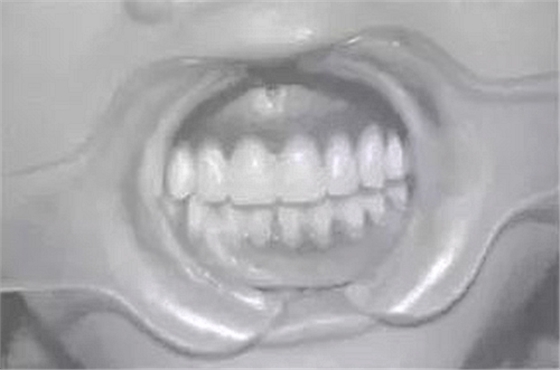

預約定時復診。完成修復后,囑患者注意合理飲食及口腔衛(wèi)生,每年復診。隨訪4年,患者自覺良好,飲食咀嚼正常,復查:臨床檢查見,16、17、26、36、46、75、85合面見充填體,26遠中面缺損平齦緣,17臨床牙冠已完全暴露于口內(nèi),27可見1/3牙冠:義齒就位后其固位及穩(wěn)定性較好、無壓痛、患者發(fā)音正常、進食正常:X線片示:75、85牙根可見根尖1/3處發(fā)生吸收、17、27牙根未發(fā)育完全;牙槽骨未發(fā)現(xiàn)吸收情況;同4年前相較而言,戴用義齒后,牙槽骨可見輕微增長。

圖3修復后口內(nèi)像